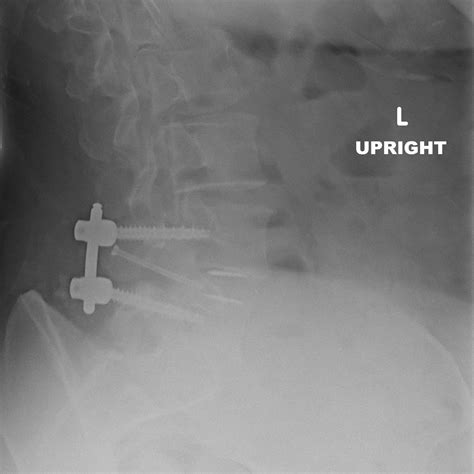

PLIF vs. TLIF: Which is Better?